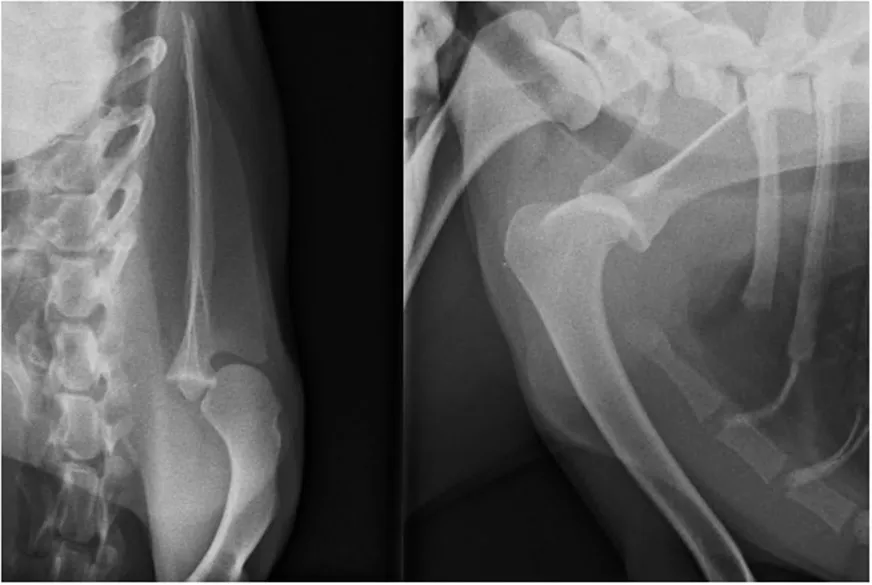

Teşhis

Deneyimli bir cerrah teşhisi fiziksel muayene ve inspeksiyon aracılığıyla koyabilir. Tecrübeli gözler yürüme esnasında topallığun ‘’omuz topallığı’’ olduğunu fark edecektir. Muayene ile teşhis sonrası röntgen çekimleri ile varolan teşhisi desteklemek gerekir. Ayrıca osteoartrit varlığının tespiti için de röntgen görüntüsü elzemdir.